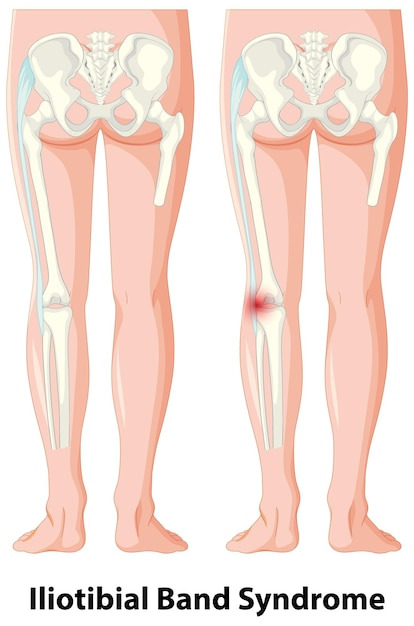

잘못된 자세, 불균형한 운동, 스트레스 등 다양한 원인으로 인해 골반이 틀어질 수 있습니다. 틀어진 골반은 허리 통증, 다리 길이 차이, 소화불량 등 다양한 건강 문제를 야기할 수 있습니다.

- 골반 틀어짐은 허리 통증, 디스크, 척추 측만증 등 다양한 질병을 유발할 수 있습니다. 꾸준한 운동과 함께 다음과 같은 생활 습관을 실천하여 질병을 예방해야 합니다.